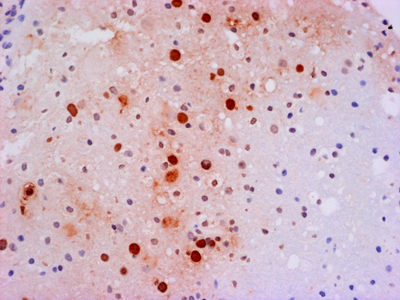

There may be as many clinical definitions for dementia as there are pathological definitions for neurodegeneration. A simple clinical definition of dementia might be “a chronic irreversible encephalopathy affecting multiple cognitive domains” (memory being the most prominently involved domain in the most common form of dementia, Alzheimer’s disease [AD]). Clinical dementias can be measured with a variety of clinical scales but are most commonly appreciated from the perspective of impaired capacity to perform activities of daily living. A simple pathological definition of neurodegeneration could encompass loss of neurons, their axonal connections or synapses, but given difficulties in quantifying these degenerative changes, current pathological diagnoses rely on distinctive histopathology (Figure 1) [2, 3]. With recent refinements in our understanding of dementia and neurodegeneration, is there support for an infectious etiology in age-related dementias?

Figure 1. Bielschowsky-stained section of neocortex from a patient with Alzheimer’s disease. Individual pyramidal neurons show intense staining of neurofibrillary tangles in cell bodies and proximal processes. Neuropil plaques show staining of dystrophic neuritic processes. There are no infiltrating adaptive immune cells.